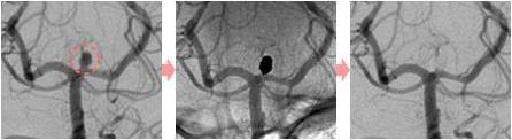

脳動脈瘤塞栓術

脳動脈瘤が破裂して出血するのを防ぐために、脳動脈瘤にコイルを詰めて血液が入り込まないようにする手術です。

術後に血管撮影を行うと、コイルで置き換わった脳動脈瘤は造影剤が入らないため描出されなくなります。